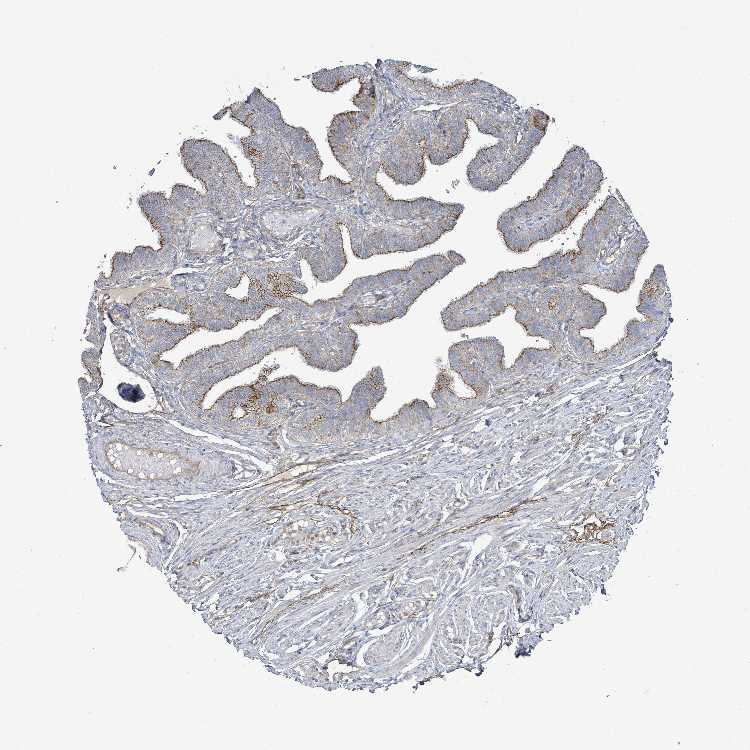

FALLOPIAN TUBE - Antibody stainingi

Antibody staining in the annotated cell types in the current human tissue is reported as not detected, low, medium, or high, based on conventional immunohistochemistry profiling in selected tissues. This score is based on the combination of the staining intensity and fraction of stained cells.

Each image is clickable and will lead to virtual microscopy that enables deeper exploration of all samples and also displays staining intensity scores, fraction scores and subcellular localization as well as patient and tissue information for each sample.

Antibody HPA050716

Ciliated cells (cell body) High

Ciliated cells (cilia axoneme) Not detected

Ciliated cells (ciliary rootlets) Not detected

Ciliated cells (tip of cilia) Not detected

Non-ciliated cells High